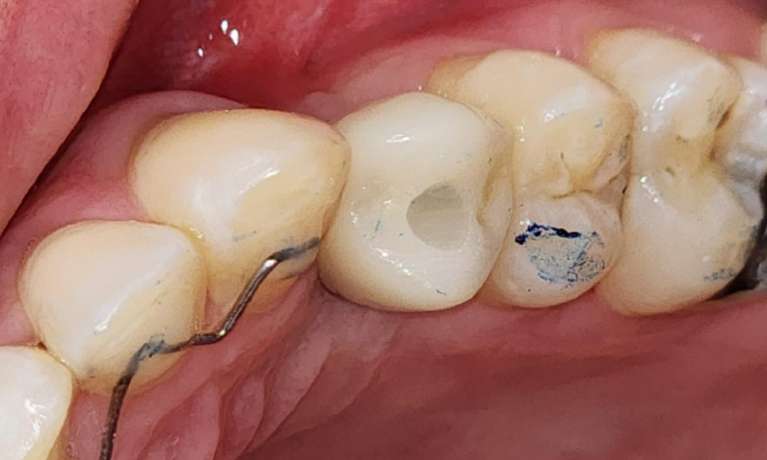

For this patient, dental implants were used to replace missing back teeth to help reestablish chewing efficiency and improve overall oral function.